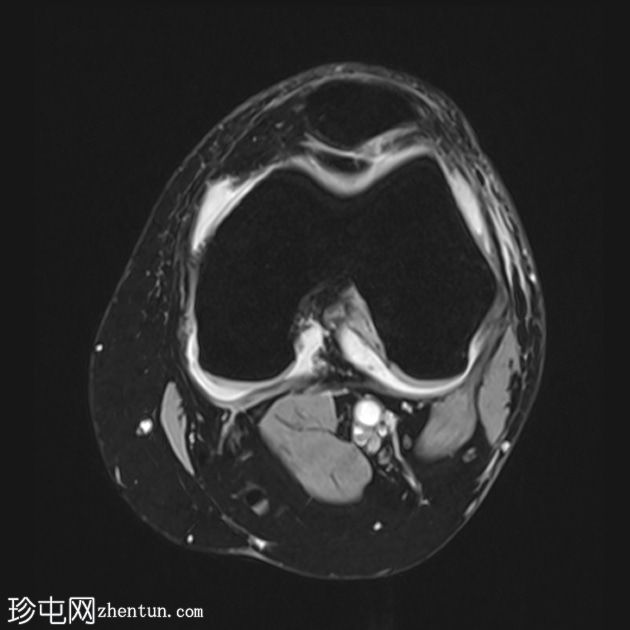

轴位PD序列

脂肪抑制序列

轴位

T2-ME3D-WE序列

外侧半月板后角和体部存在完全纵向撕裂,导致大部分后角翻转至髁间窝。

体部翻转至截断的前角后方。这导致后方出现“半月板幽灵征”。

矢状位图像上可见前方双三角征,髁间区可见双PCL征。